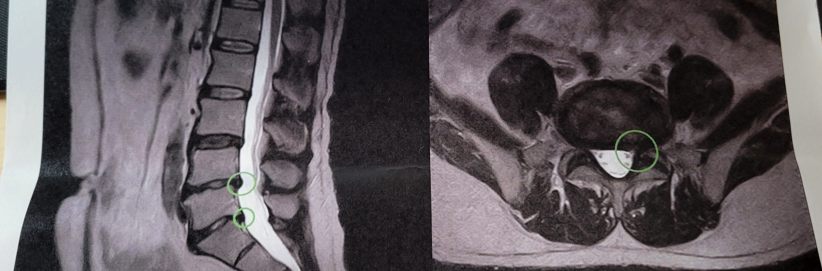

結果は……

腰のヘルニアですね、そんなに酷くは無いらしい。手術は必要なしとのこと。しばらくリハビリに来てくださいと。週2回でも3回でも!と若いドクターに強く勧められましたがそんなに来れんて(苦笑) せいぜい週1回だよね……と。そこはドクターの代わりに話をした看護師さんと(笑)